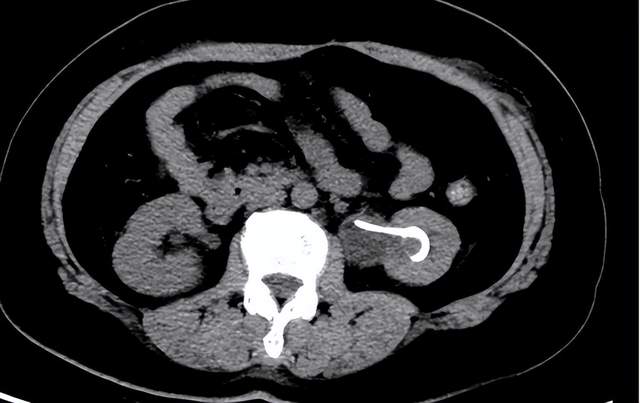

术后复查CT

科室副主任张如钢副主任医师详细分析病情后,发现存在两大矛盾点。一是影像学矛盾:泌尿系增强CT显示左侧输尿管下段仅见3mm微小结石,但输尿管全程显著扩张、肾积水程度与结石梗阻情况严重不符;二是解剖矛盾:输尿管镜探查时发现下段距膀胱入口2cm处完全闭锁,镜体无法通过,证实存在输尿管狭窄闭锁。